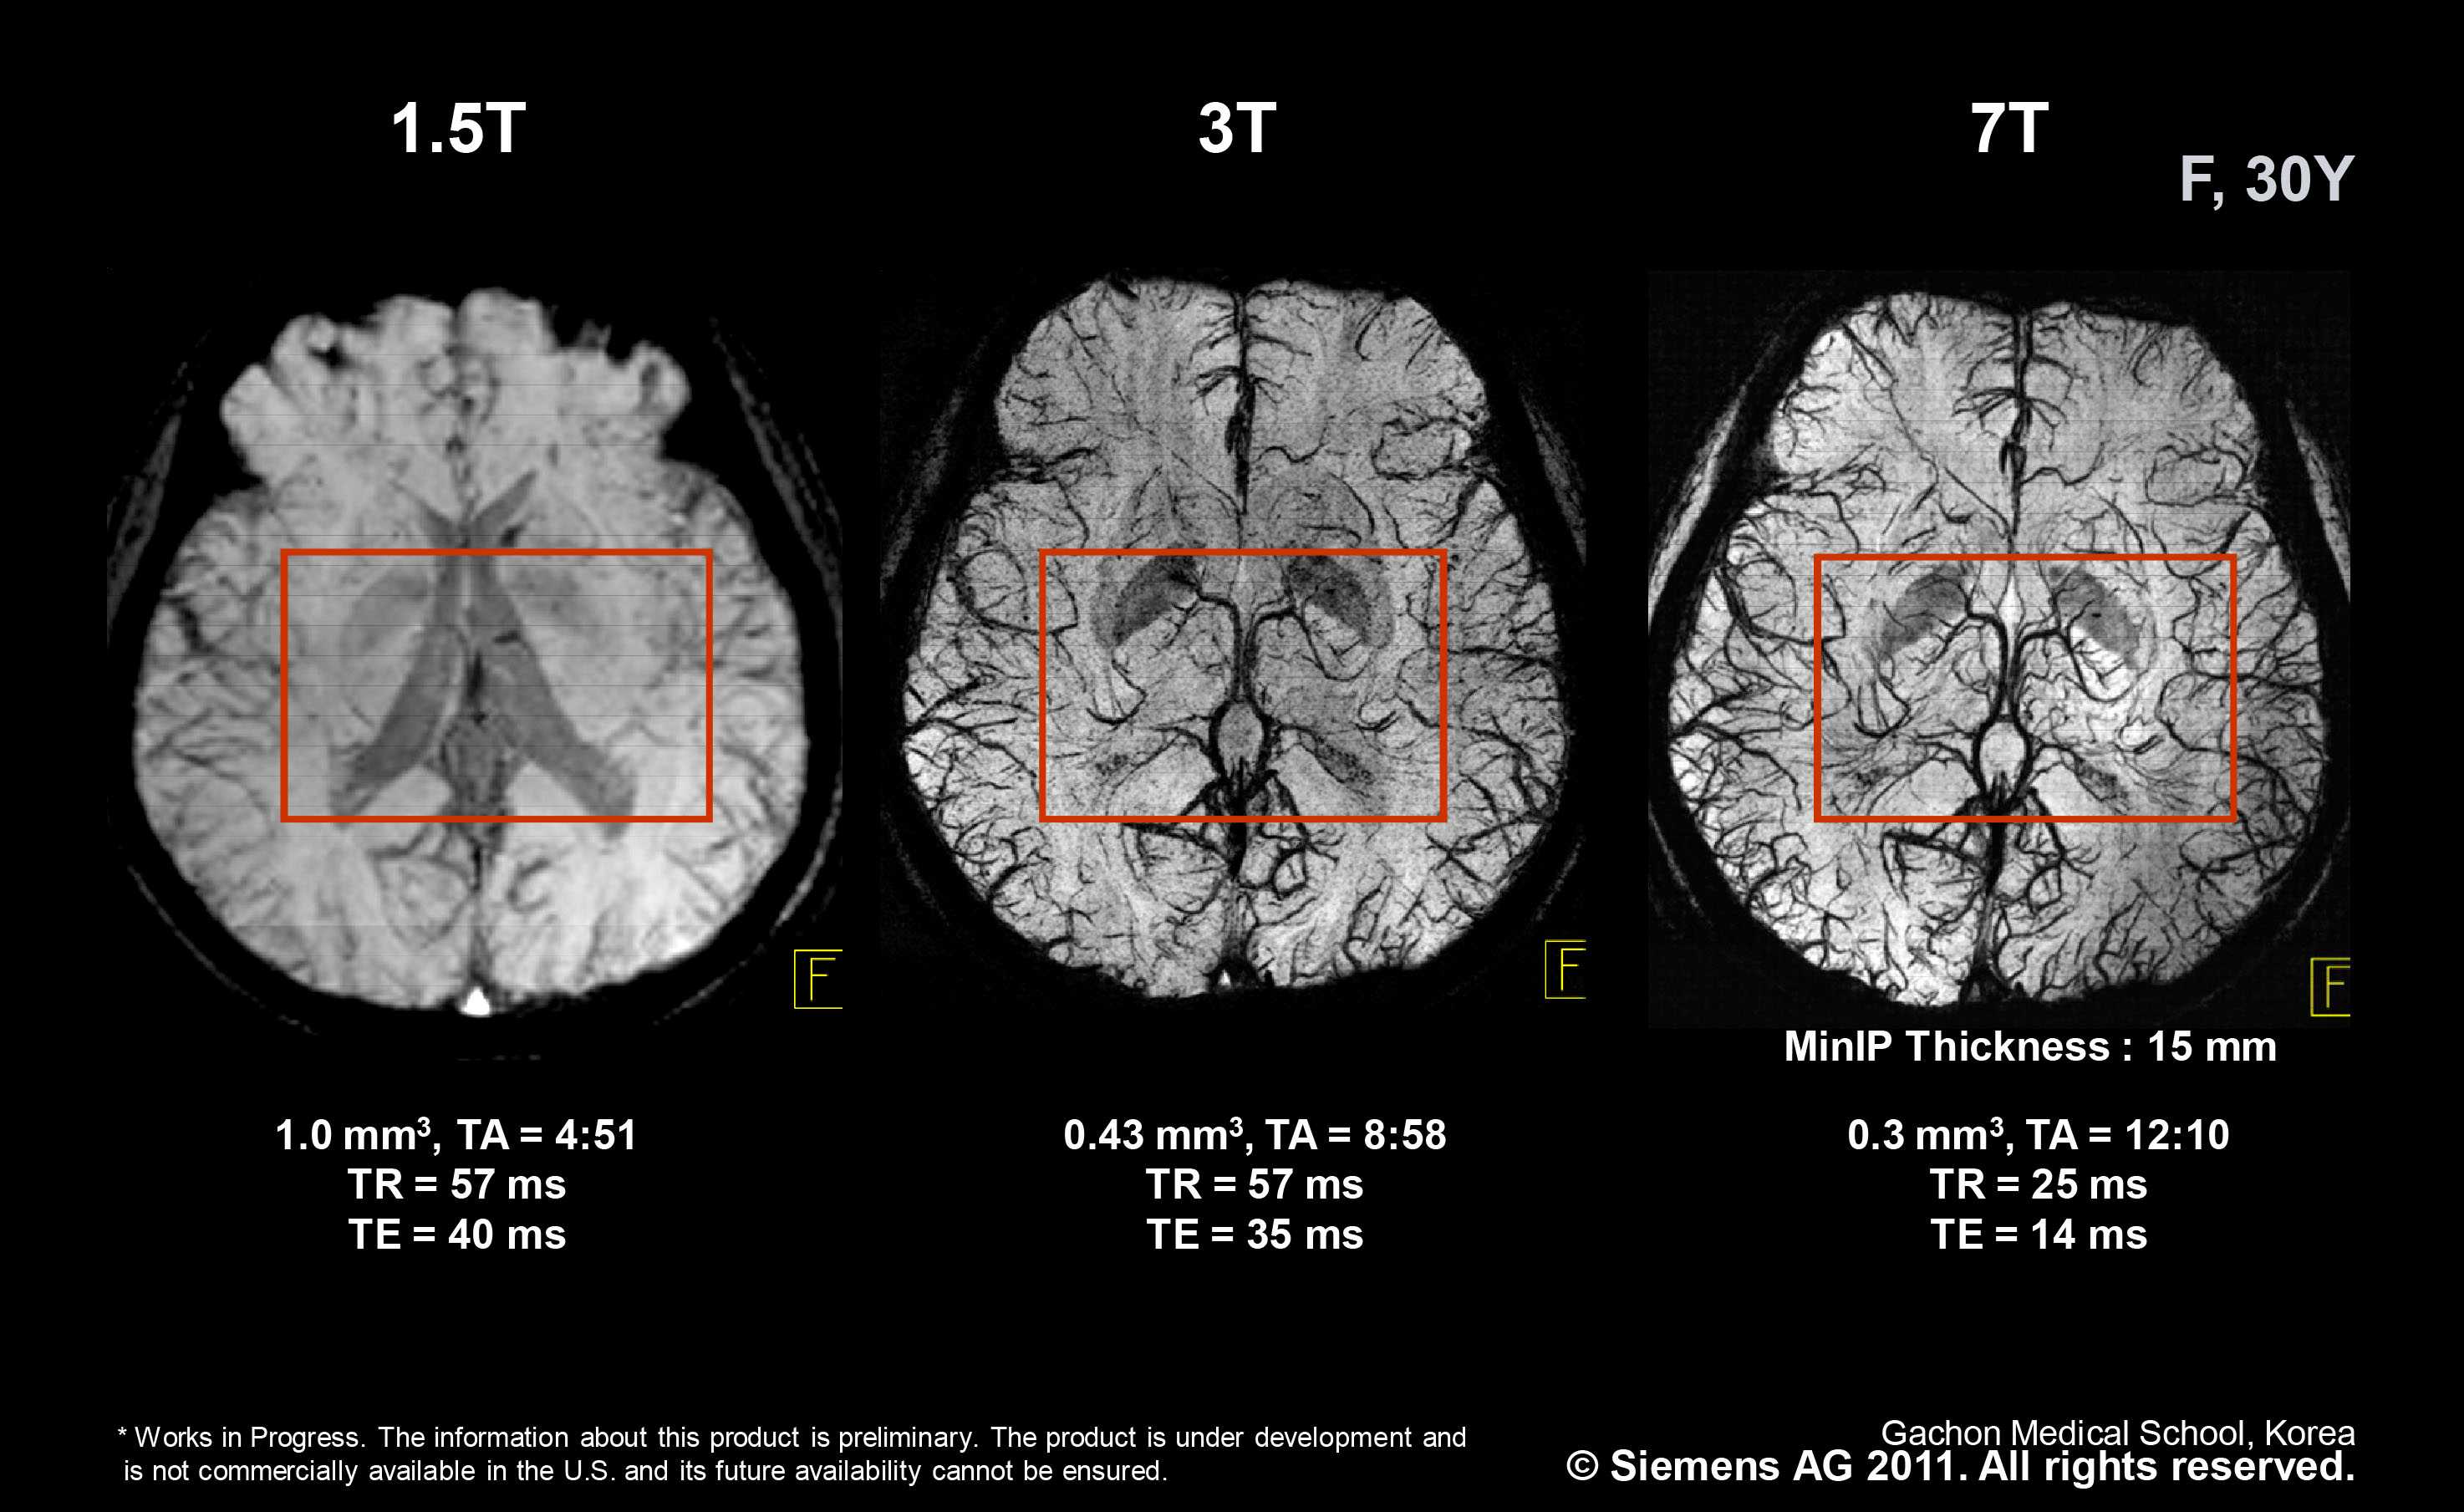

The higher resolution of the 3 Tesla MRI produces more. With a magnetic field strength that is twice as powerful as a 15T the 3T MRI provides. The T in 15T and 3T MRI machines is in reference to the tesla which is used to measure the strength of the magnet used in the MRI machine.